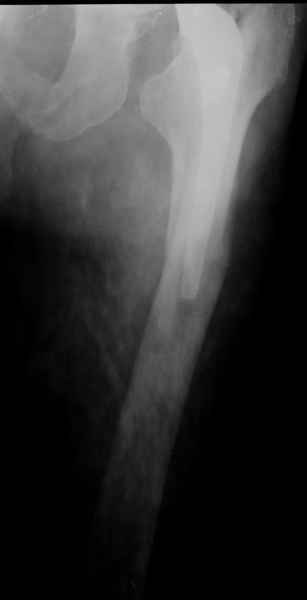

Уважаемые коллеги, продолжая дискуссию, начатую на "Вреденовских чтениях", хочу сказать, что принципиально сущестует два возможных варианта лечения.

1.Остеосинтез на ножке. Мне кажется, что применительно к этому случаю малоперспективный вариант. Синтез хорош, когда можно его выполнить в малоинвазивном исполнении и достигнуть стабильности. Действительно, если ножка б/цементной фиксации после этого не будет иметь фиксации, то ревизия не будет иметь проблем. В представленном случае стабильность синтеза сомнительная, а проведение доп.иммобилизации приведет к контрактуре суставов.

2. Применение ножки дистальной фиксации, мы отдаем предпочтение ножке Вагнера с фиксацией проксимального отдела на ножке. Более травматичное вмешательство, но при стабильной фиксации ножки реабилитация идет в обычном режиме.

Хочется показать два подобных случая, П-ка З. 72 лет и п-т Г. 80 лет. Сразу принимаю замечание, что это были ножки цементной фиксации, просто под руками не было бесцементника.